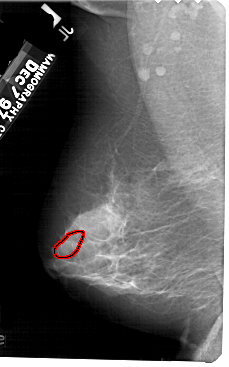

FILE: A_1584_1.LEFT_MLO.OVERLAY

TOTAL_ABNORMALITIES 1

ABNORMALITY 1

LESION_TYPE CALCIFICATION TYPE PLEOMORPHIC DISTRIBUTION SEGMENTAL

ASSESSMENT 4

SUBTLETY 4

PATHOLOGY MALIGNANT

TOTAL_OUTLINES 2

BOUNDARY